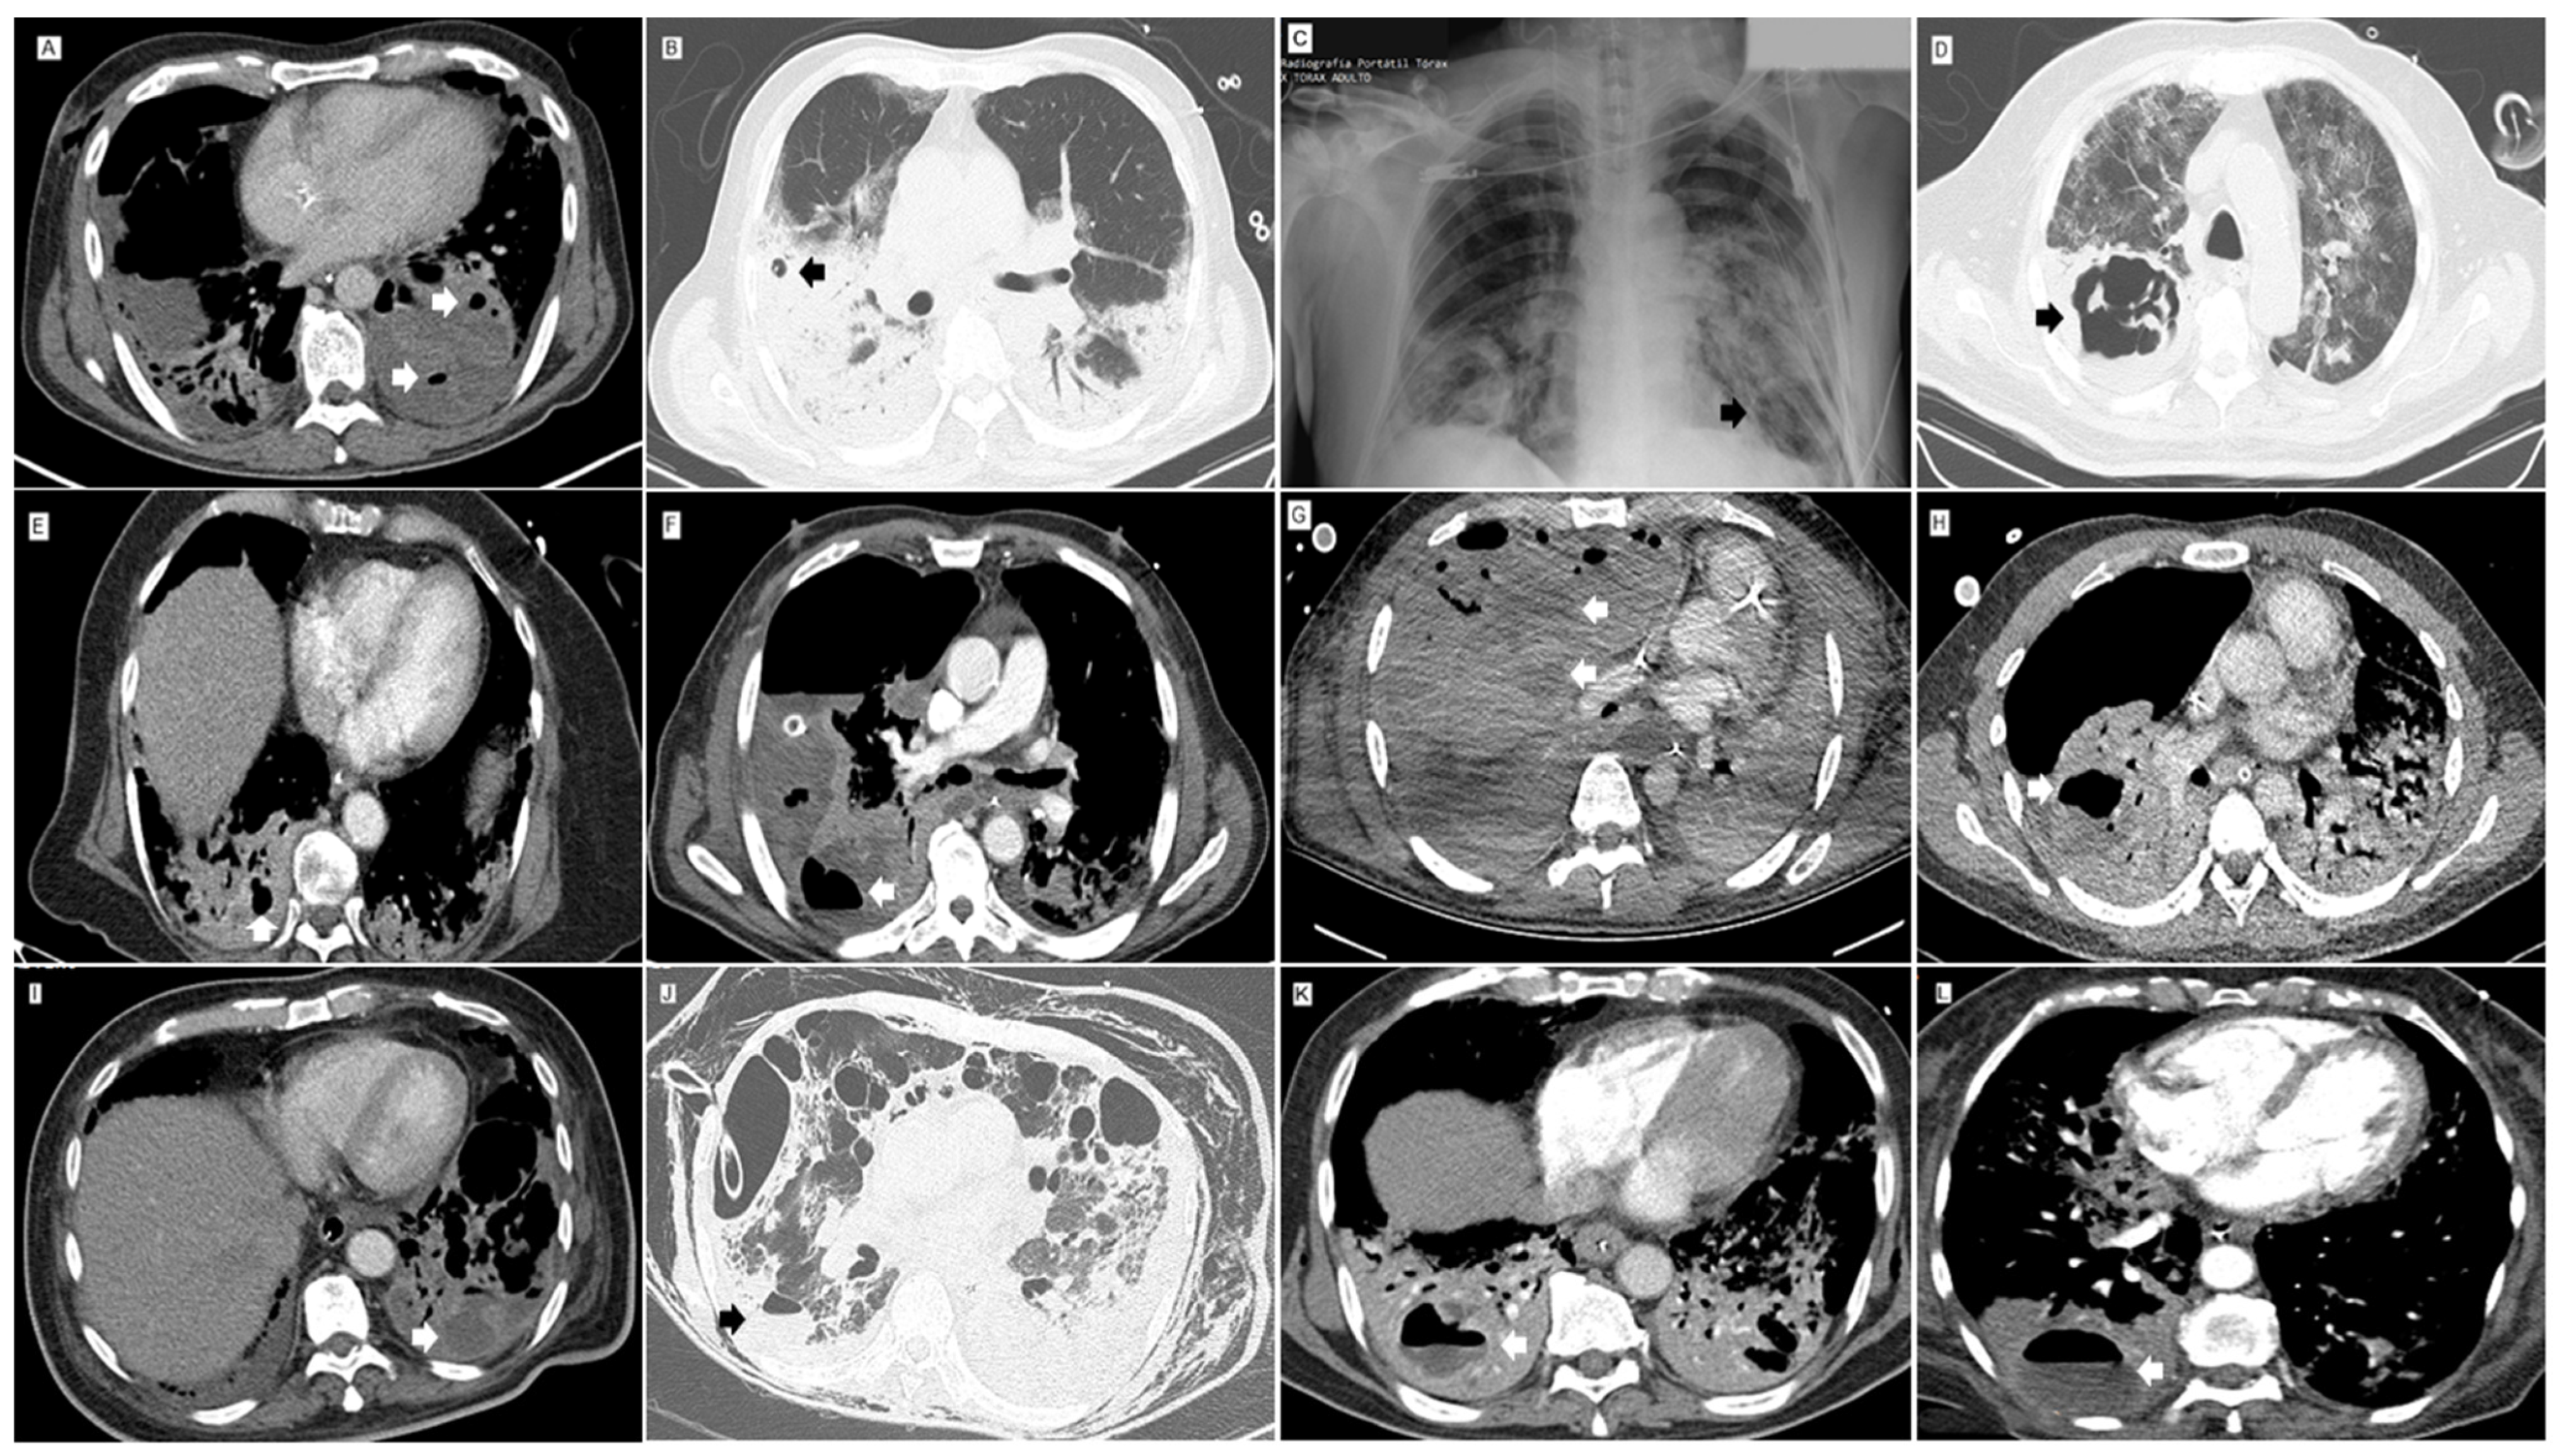

| Imaging and/or surgical findings n (%) * | |

| Abscess | 21 (50.0) |

| Mediastinal/hilar adenopathies | 20 (47.62) |

| Cavity | 17 (40.48) |

| Pneumatocele | 16 (38.1) |

| Pneumothorax | 15 (35.71) |

| Pulmonary embolism | 13 (30.95) |

| Bronchopleural fistula | 11 (26.19) |

| Empyema | 9 (21.43) |

| Pulmonary infarction | 8 (19.05) |